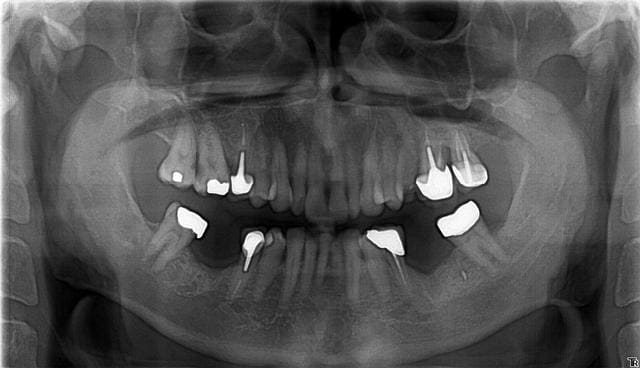

Pano y6gwjv - Eugenol

Sur la simulation que je joins, j'ai placé 2 implants 5.2 x 6.5 pour 36 et 46 en unitaire.

De plus rien à voir avec le radiologue mais on nous montre une planification 3D avec Simplant qui utilise les images 3D réelles des implants à poser replacé sur le scan.

Donc il n'y a pas de "à peu près" c'est comme ça et puis c'est tout :-))

Simplant propose une marge de sécurité (qui couine et qui s'affiche) quand on se rapproche trop du NAI, sur cette planification elle n'apparait pas et cje pense que c'est toujours mieux de garder cette alarme active ;-)